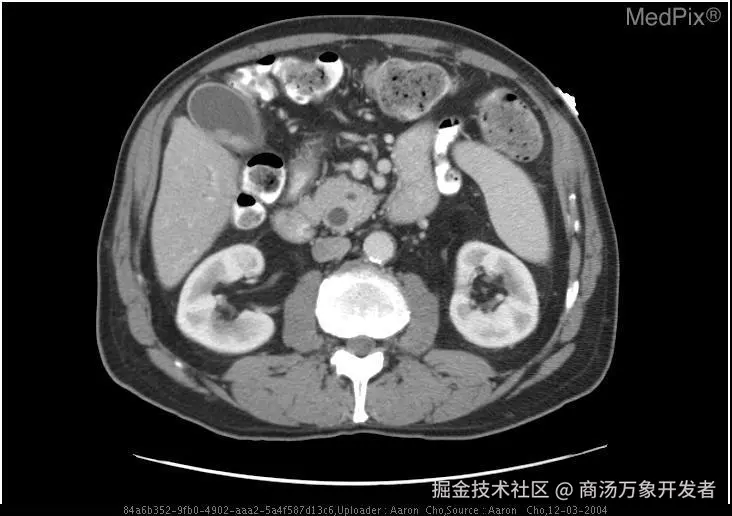

🔧数据集简介

VQA-RAD 是一个关于放射影像的问题-答案对数据集(huggingface.co/datasets/fl… )。

ee23254b20102bfa8c6de8d1925a8768.png

训练集测试集

问题1,793451

图像313203

🚀 数据集用途

• 训练和测试医学影像VQA(视觉问答)系统

• 支持开放式问题(如“病灶位置?”)和二元问题(如“是否存在肿瘤?”)

🔍 数据来源

• 基于MedPix(开放医学影像数据库)

• 由临床医生手动标注,确保专业性

🌟 核心优势

• 首个专注放射影像的VQA数据集

• 结构清晰,覆盖临床常见问题类型